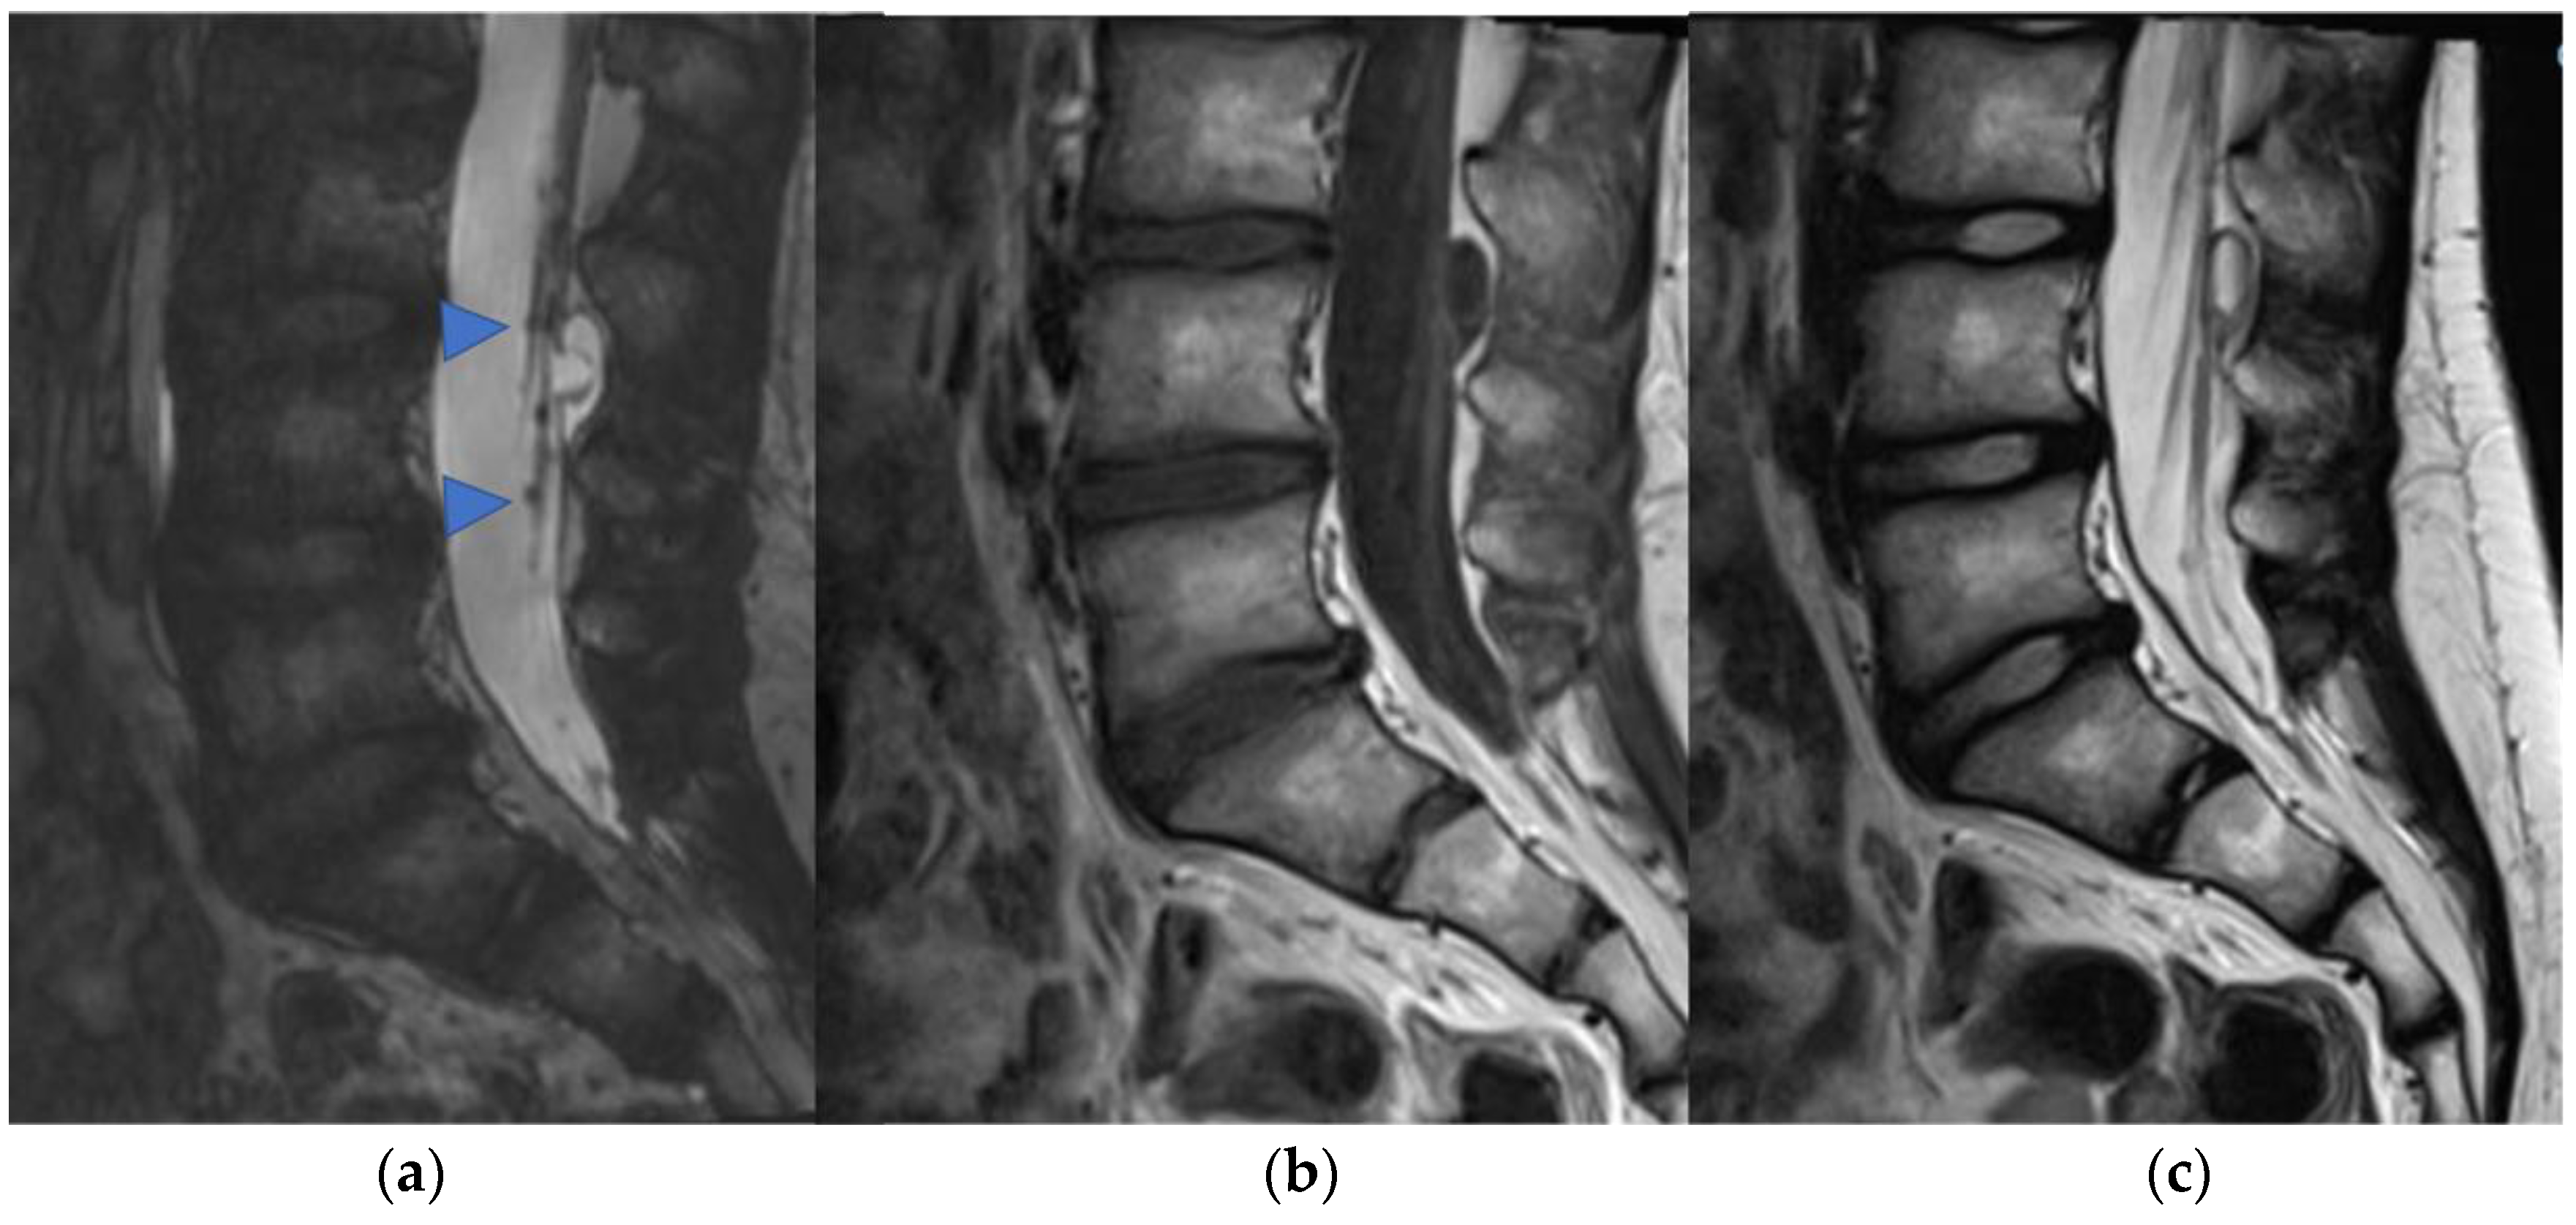

An intradural-extramedullary neoplasm, myxopapillary ependymoma (Figure 8), is typically located in the lumbo-sacral region due to its origin in the filum terminale [34]. This subtype represents 13% of all spinal ependymomas and can also extend into the neuroforamina, thus differential diagnosis includes extradural tumors [3].

Figure 8.

Myxopapillary ependymoma in a fourteen-year-old child located in the lumbo-sacral region. Sagittal T2-weighted (a) and post-contrast T1-weighted (b) images demonstrate solid cranial and caudal enhancing components (blue arrows) and a pseudocystic non-enhancing component (arrowhead). The detail of the filum terminale is also highlighted (white arrow).